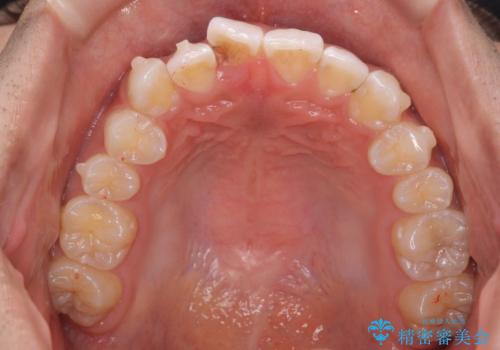

前歯のがたつき 1年かからず治療 マウスピース矯正

- 前歯のがたつきを主訴に来院。

インビザラインで歯を抜かずに並べました。

マウスピースの延長(リファインメント)もなく、短期間で綺麗に並びました。